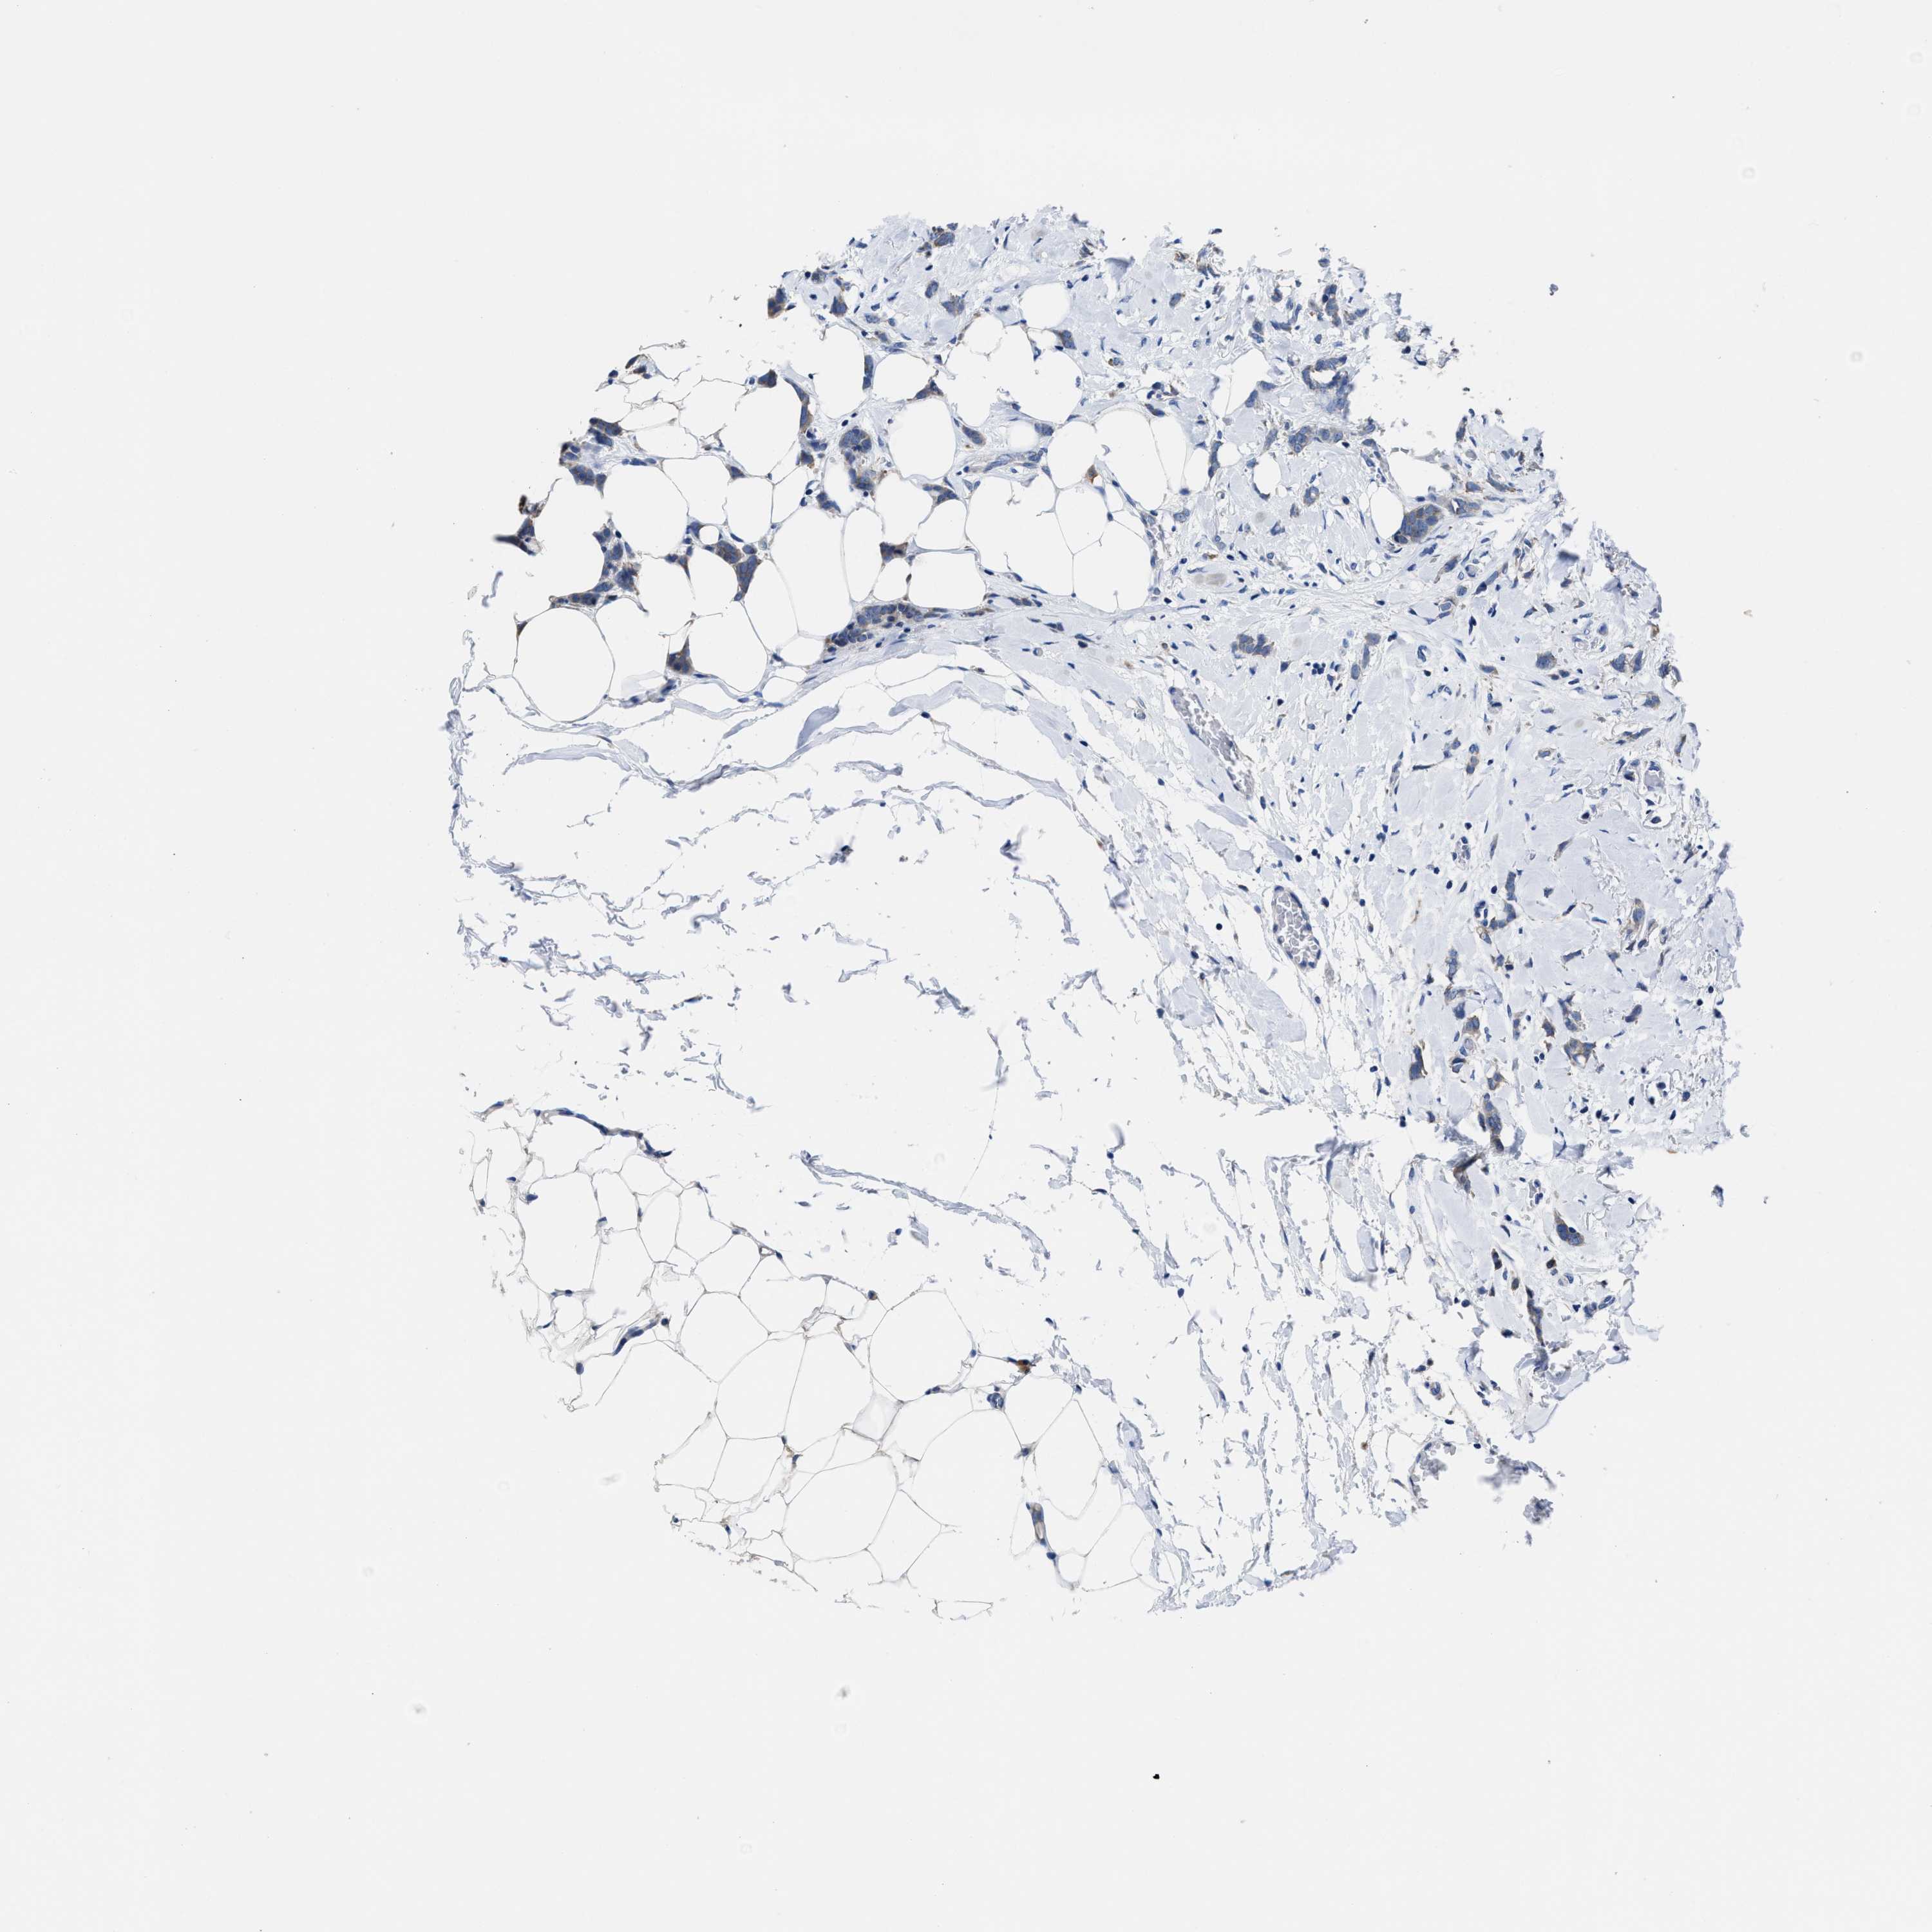

BRCA TCGA BRCA VALIDATION PROTEIN EXPRESSION